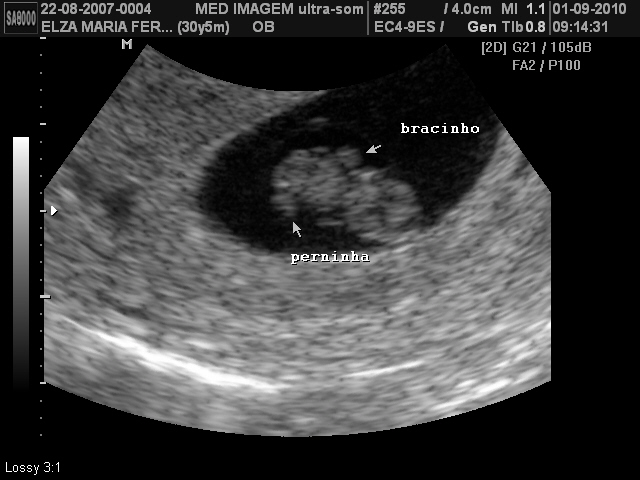

Olha o meu bebê aí...

Ontem foi nosso 1° ultrasson oficial, pois da primeira vez não deu pra ver! Que alívio foi saber que está tudo bem com esta gestação e com o bebê. Deu até para ver o bracinho e a perninha em pleno desenvolvimento! Meu marido não parava de sorrir e levou as fotos para o trabalho para mostrar pra todo mundo.

O médico até mesmo conseguiu pegar uma imagem que ele disse ser rara, conseguimos ver a divisão do 2° líquido onde o bebê está, é uma espécie de bolha, e por ser uma linha tênue, muitas vezes o ultrassom não consegue captar essa imagem. Mas meu bebê colaborou, rsrsrs:

Vocês conseguem ver? Ele até circulou, pois é quase imperceptível.